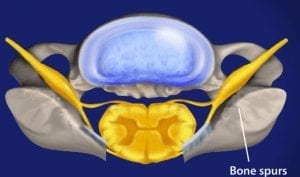

Irregular bone growth that grows in the vertebrae. They develop mostly because of friction that occurs within joints

Irregular bone growth that grows in the vertebrae. They develop mostly because of friction that occurs within joints